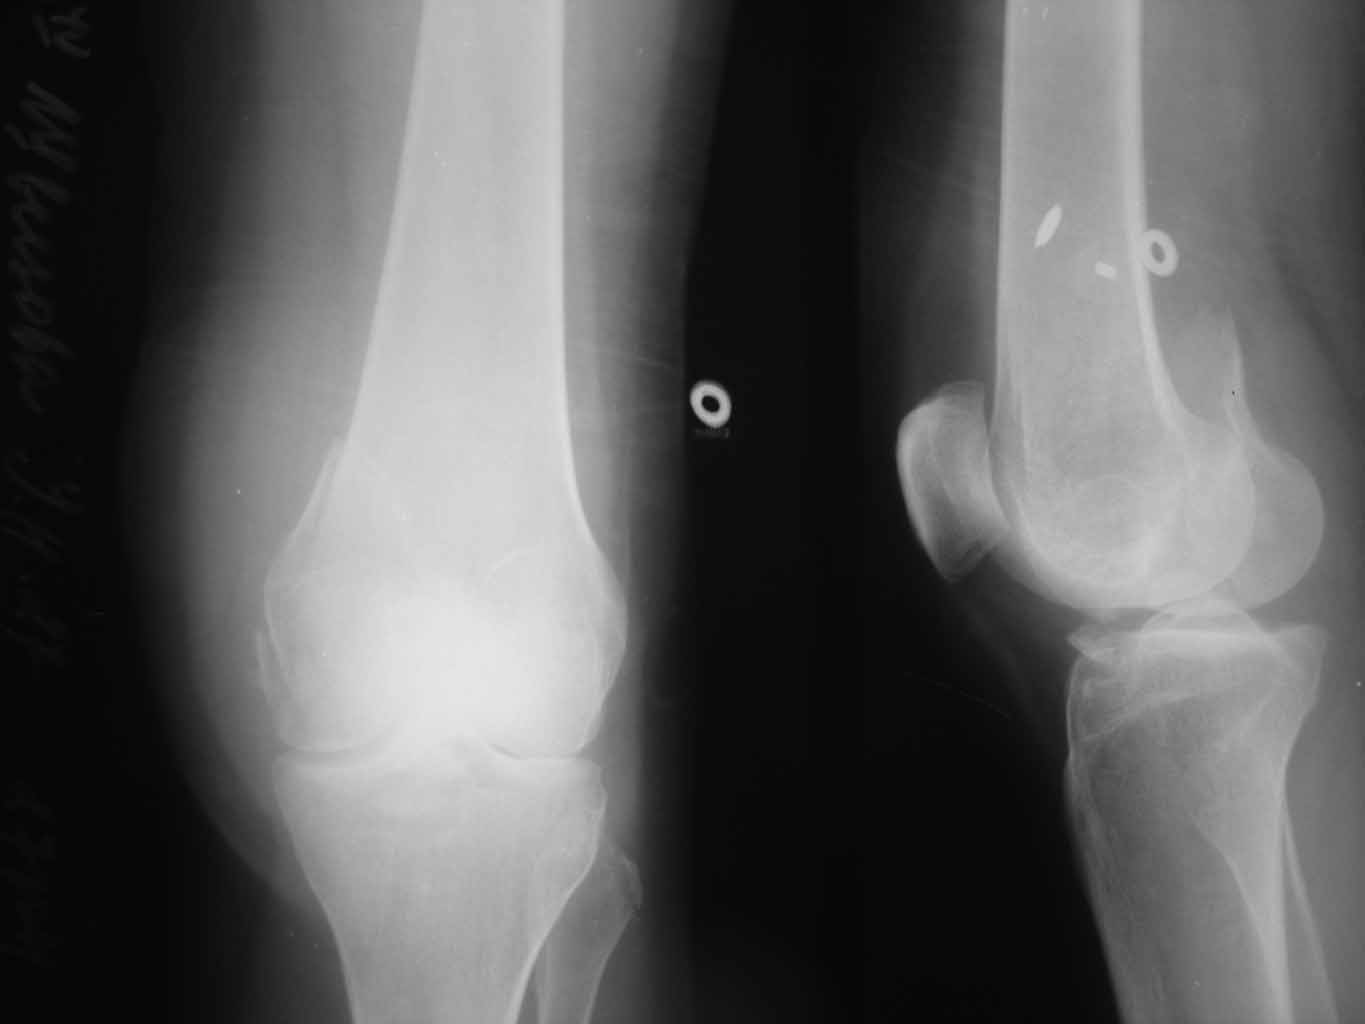

медиальный перелом мыщелка бедра |

Уважаемые коллеги!!!!Хотелось бы услышать мнения...Закрытый перелом медиального мыщелка бедра от 28.10.11. Здравствуйте, уважаемые коллеги! Просим помочь!!! В отделение поступила пациентка 27 лет с переломом медиального мыщелка бедренной кости, была сбита автомобилем. Планируем оперативное лечение. Подскажите пожалуйста, какой фиксатор предпочтительнее выбрать при данной локализации перелома, каким доступом выполнить репозицию отломка, возможна ли фиксация отломка дистальной бедренной пластиной, есть ли фиксаторы именно для медиального мыщелка бедра? ЭОП есть, финансовые возможности у пациентки есть. Если у вас найдутся рентгенограммы похожих случаев, пожалуйста, скиньте в обсуждение, будем очень признательны. Спасибо! Ждем ваших комментариев!

Обратите также внимание на перелом головки малоберцовой кости и фрагмент передней части межмыщелкового возвышения - это может быть повреждение связок: ПКС и наружной боковой.

Вроде перелом идентичный, и зачем выдумывать несуществующие специальные импланты, можно применить обычную 1/3 tubular plate, медиальный доступ, цена импланта $37 и шурупы к ним $50-80, а “Ортопедический Оргазм” бесценный.

Добрый вечер!!!Огромное спасибо за совет.Пациентку прооперировали, перелом к счастью оказался изолированным,но между большим фрагментом оказалось несколько мелких фрагментов, что довольно затруднило репозицию( в операционной нет ЭОП), но все успешно.Спасибо!!)))фиксировали реконструктивной пластинкой и спонгиозным 7.0 мм винтом,получилось стабильно.